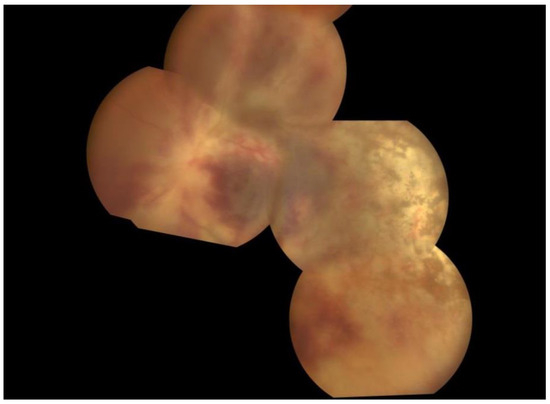

A 32-year-old Caucasian man presented at the Ophthalmology Department complaints of decreased vision and ocular pain accentuated during movement that appeared a day before. A week before the onset, the patient also had symptoms specific to a transient ischemic attack, with the loss of muscle force on the right upper limb and aphasia. On ocular examination, his vision in the right eye was 6/6 and in the left eye was HM (hand motion). Slit lamp biomicroscopy, which represent the instrument used to examine the anterior and posterior segments of the eye under high magnification, showed signs of anterior uveitis, with discrete corneal endothelial edema and micro Tyndall, in the right eye and severe corneal endothelial edema—granulomatous inferior inflammatory cells deposited on the cornea-keratic precipitates—and moderate Tyndall in the left eye. Fundus examination showed a small peripapillary infiltrated zone of white necrosis and in the extreme nasal periphery a zone of white necrosis with edema located along the distribution of retinal vessels in the right eye. In the left eye, the fundus examination showed pseudopapilledema, with hemorrhagic necrosis on white/yellow cloudy retinal lesions, centered around vasculature (Figure 1). OCT of the left eye showed necrosis of the fovea, resulting in significant destruction of the retinal nerve fiber layer.

Figure 1.

Fundus photographs of the right and left eyes. At presentation, the right eye shows small peripapillary infiltrated zone of white necrosis and the left eye shows pseudopapilledema, with hemorrhagic necrosis on white/yellow cloudy retinal lesions.